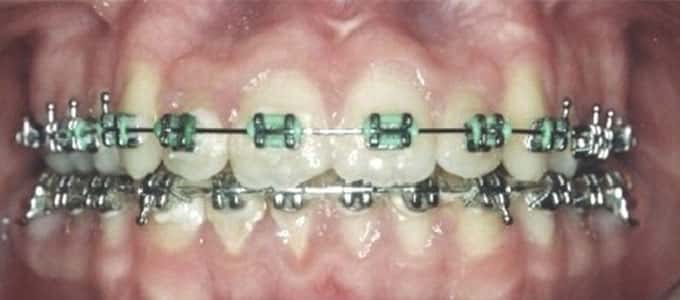

Aparatul fix metalic

Este cel mai des întâlnit tip de aparat, brackeții sunt fabricați din diverse aliaje metalice inoxidabile, așadar se văd cu ușurință. Cu toate acestea, aparatul fix metalic are o serie de avantaje demne de luat în considerare:

- durata de tratament mai scurtă

- brackeții sunt mai micuți si jenează mai puțin

- costurile sunt mai mici

- singurul dezavantaj al acestui tip de aparat este dat de aspectul estetic (brackeții sunt vizibili pe dinți)